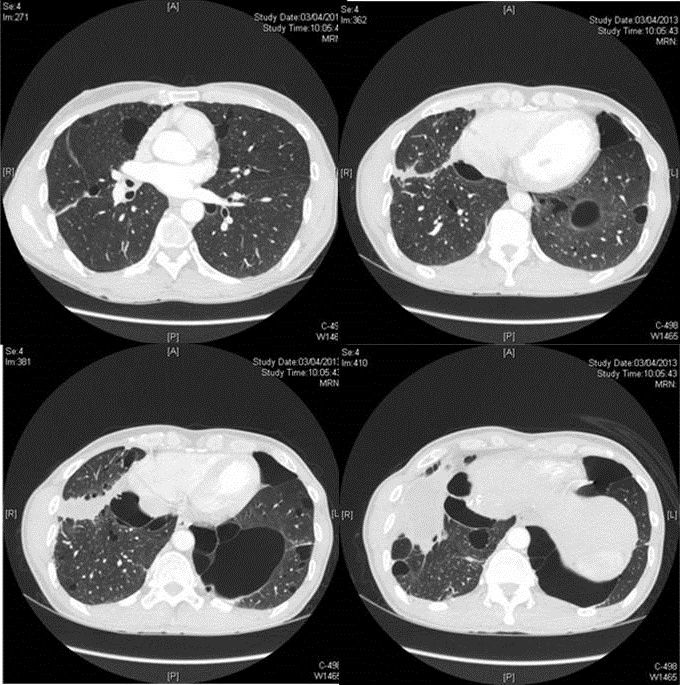

Figure 2 HRCT showing multiple bullae

There was a pleural collection with multiple foci of high attenuation at right lung base and was compatible with previous talc pleurodesis. Large bullae were present bilaterally. Diagnostic pleural tapping was performed and the pleural fluid was negative for AFB smear, culture and cytology.